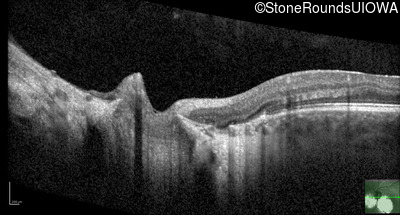

Age at visit: 5 weeks (Visit 2)